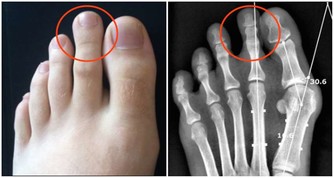

3,眼睛模糊;指甲表面有凸起的棱線,或者凹陷

肝主目,肝血不足則不能視,夜盲症也是這樣。肝主筋,爪(指、趾甲)為筋之餘,如果肝血不足,指甲則會出現棱線、凹陷、沒有血色、手握無力。